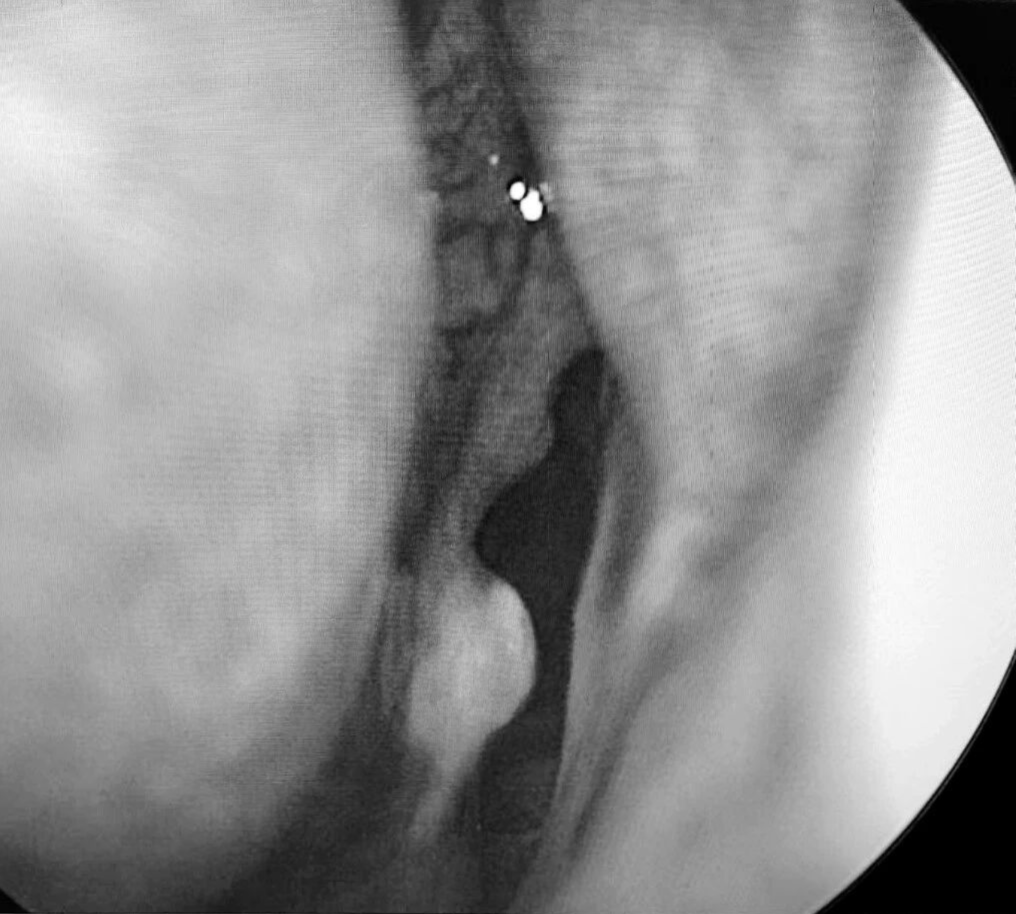

患者梁某(化名)因反复鼻塞、流脓涕伴头痛2月余入院,经检查确诊为急性鼻窦炎、双侧乳突炎,药物治疗后症状未缓解且并发筛窦脓肿到我院耳鼻咽喉科二区住院,科室团队快速完成术前评估,为患者制定个性化手术方案,在全麻下精准实施经鼻内镜手术,开放病变窦腔、清理脓液,术中损伤小,仅用吸收性明胶海绵止血。术后通过专业的鼻腔冲洗指导、药物治疗管理及定期内镜复查,有效促进术腔黏膜修复,降低复发风险,助力患者实现快速康复。

我院耳鼻咽喉科二区以微创内镜手术为特色,面对急性鼻窦脓肿这类需及时干预的病症,能通过高效术前评估、优化手术流程,精准去除病灶,避免并发症发生。手术前后规范用药配合专业术后护理,包括鼻腔冲洗指导与定期内镜复查,有效降低复发风险,践行快速康复外科理念。